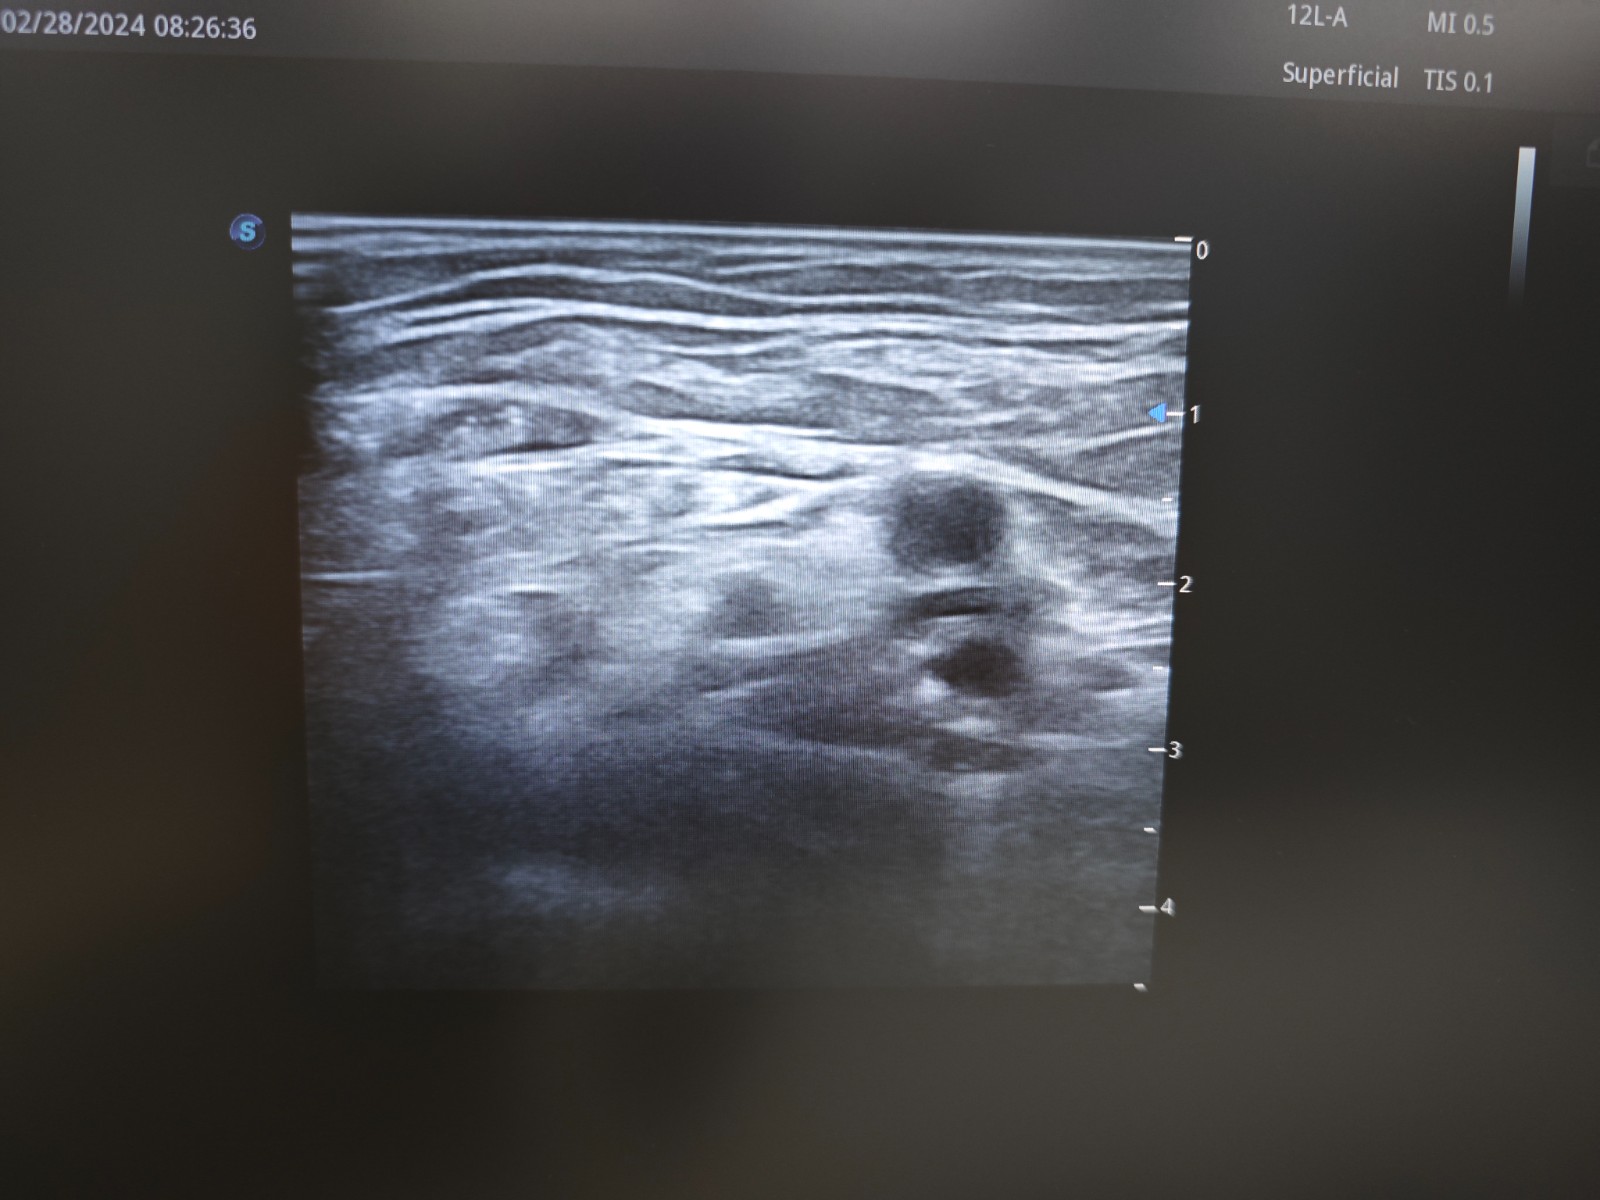

髂筋膜阻滞超声图像

髂筋膜间隙是一个潜在的腔隙,其后方以髂腰肌为界,前方以髂筋膜为界,髂筋膜浅层以阔筋膜覆盖。股神经和股外侧皮神经、闭孔神经在骨盆节段都位于髂筋膜下方。髂筋膜间隙阻滞是相对简单的技术,可以作为股神经阻滞或腰丛阻滞的补充,其机制是股神经和股外侧皮神经、闭孔神经都位于髂筋膜下方,在髂筋膜下注射足量的局麻药,即使位置离神经较远,局麻药也可在髂筋膜下方扩散,到达这些神经。髂筋膜间隙阻滞的范围有赖于局麻药的扩散程度和被阻滞的神经。股神经阻滞会阻滞到髋关节和膝关节的关节支,从而阻滞髋关节的疼痛,股外侧皮神经阻滞会阻滞大腿外侧的皮肤感觉,就可以缓解老年患者髋部骨折的疼痛了。